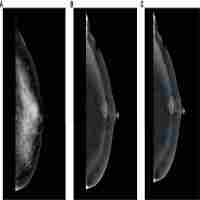

| Abstract | Background Radiomics plays an important role in the field of oncology. Few studies have focused on the identification of factors that may influence the classification performance of radiomics models. The goal of this study was to use contrast-enhanced mammography (CEM) images to identify factors that may potentially influence the performance of radiomics models in diagnosing breast lesions. Methods A total of 157 women with 161 breast lesions were included. Least absolute shrinkage and selection operator (LASSO) regression and the random forest (RF) algorithm were employed to construct radiomics models. The classification result for each lesion was obtained by using 100 rounds of five-fold cross-validation. The image features interpreted by the radiologists were used in the exploratory factor analyses. Univariate and multivariate analyses were performed to determine the association between the image features and misclassification. Additional exploratory analyses were performed to examine the findings. Results Among the lesions misclassified by both LASSO and RF ≥ 20% of the iterations in the cross-validation and those misclassified by both algorithms ≤5% of the iterations, univariate analysis showed that larger lesion size and the presence of rim artifacts and/or ripple artifacts were associated with more misclassifications among benign lesions, and smaller lesion size was associated with more misclassifications among malignant lesions (all p < 0.050). Multivariate analysis showed that smaller lesion size (odds ratio [OR] = 0.699, p = 0.002) and the presence of air trapping artifacts (OR = 35.568, p = 0.025) were factors that may lead to misclassification among malignant lesions. Additional exploratory analyses showed that benign lesions with rim artifacts and small malignant lesions (< 20 mm) with air trapping artifacts were misclassified by approximately 50% more in rate compared with benign and malignant lesions without these factors. Conclusions Lesion size and artifacts in CEM images may affect the diagnostic performance of radiomics models. The classification results for lesions presenting with certain factors may be less reliable. |